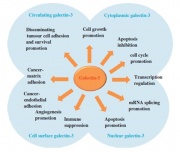

| 10:44, 11 באוגוסט 2014 | גלקטין2.jpg (קובץ) |  |

44 קילו־בייטים | Nachi | 1 | |

| 10:42, 11 באוגוסט 2014 | גלקטין1.jpg (קובץ) |  |

32 קילו־בייטים | Nachi | 1 | |